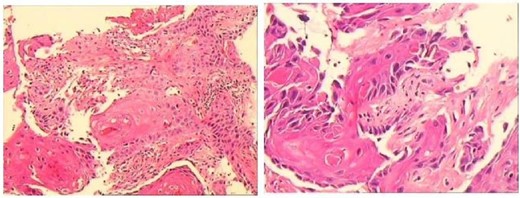

A 43-year-old male patient was admitted in July 2022 due to an anal fistula. The patient had a 15-year history of recurrent perianal abscesses with prior surgical intervention in 2007, 2011, and 2012. However, following each surgery, the wounds failed to heal completely, resulting in persistent drainage of purulent fluid through the external orifices and intermittent recurrence of perianal abscesses. Two weeks before admission, the patient reported a significant increase in perianal pain. Notably, the patient had no history of inflammatory bowel disease, but had been diagnosed with HIV infection for 10 years. Physical examination revealed two external fistulous orifices located at the 3-o’clock and 9-o’clock positions, ~3 cm from the anal verge. Rectoscopy confirmed that the internal opening was situated within the anal crypt at the 6-o’clock position, and laboratory tests conducted upon admission did not reveal any abnormalities. Colonoscopy was performed and no underlying intestinal pathology was identified. Perianal magnetic resonance imaging revealed an intersphincteric fistula (Fig. 1).The patient underwent surgical intervention and the resected fistula tract was subjected to histopathological examination, which yielded a diagnosis of squamous cell carcinoma (Fig. 2). Consequently, the patient was not offered further surgical treatment at our institution but was referred to a specialized center for radiotherapy. During a 2-year follow-up after radiotherapy, the patient reported complete remission of the disease with no evidence of locally recurrent cancer cells. However, the surgical wound remained partially healed.